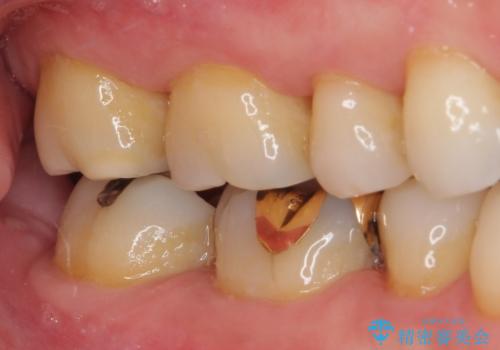

ゴールドインレーは銀歯のインレーやセラミックインレーと比べ、「技工操作の精度が高く、適合が著しく良い」というメリットがあります。特に上の奥歯は歯科医師の操作が行いにくいため、「適合の良さ」は再治療のリスクを防ぐ上でとても重要な要素となります。

上の奥歯は金属色が見えることもないため、審美的な問題は全くありません。

咬み心地はとても良好で、全く違和感がなく、患者様には大変満足していただきました。